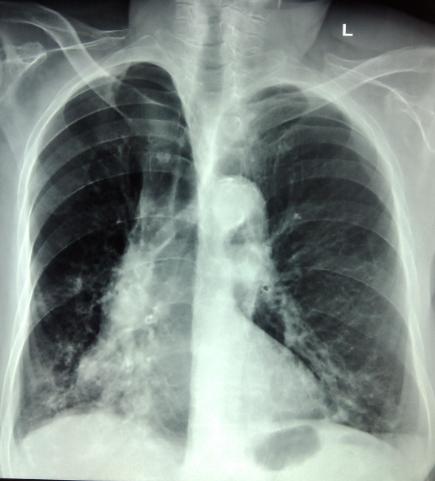

20小伙子长期抽烟,体检结果查出肺气肿!!! 20岁的身体却得了中老年人应该得的病,原来这个年轻小伙子虽然年纪不大,却是10多年的老烟民, 我们都知道肺气肿是一种常见的呼吸系统疾病,主要表现就是咳嗽,咳痰,气喘,呼吸困难,胸闷这些症状。 诱发肺气肿的主要因素有三种 第一种吸烟,吸烟是肺气肿最重要的原因,80%肺气肿由吸烟导致,吸烟者患肺气肿的可能性是非吸烟者的6倍。环境香烟(二手烟)、呼吸道感染、大气污染、职业性粉尘和有害气体的长期吸入等也是重要原因。 第二种,遗传性a1抗胰蛋白酶是长期以来公认的遗传因素,蛋白酪氨酸磷酸酶非受体6型(PTPN6) 基因的突变最近被认为是第二个引起肺气肿的基因。 第三种也考虑可由慢性肺部疾病进展而来,如哮喘、支气管扩张等, 所以建议大家尽早戒烟,为你自己,也为了家人吸入你的二手烟。 我是公立三甲医院呼吸科副主任医师吴迪, 我擅长: 1.咳嗽 2.肺结节 3.哮喘 4.慢阻肺 5.肺大泡, 6.肺纤维化 7.支气管扩张 8支气管炎 9.肺炎 10肺ai 等呼吸肺部疾病已经20多年了,别的我不擅长,肺病是我的专业。 如果你目前正在被这些问题困扰,可以给我留言,我来帮你解答。